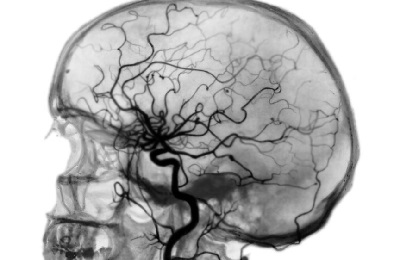

Магнитно-резонансная томография (МРТ) является одним из самых новых методов диагностики головного мозга и его сосудов, но, несмотря на небольшой срок применения, проявил себя как высокоэффективный и многообещающий диагностический метод.

Протоны водорода в молекулах воды производят импульсы, которые улавливаются мощными антеннами томографа. Все эти сигналы, поступая в компьютер аппарата, обрабатываются и преобразуются ним в отпечаток среза. Постепенно накладываясь, срезы формируют трехмерное изображение сканируемого органа.

Такое сканирование тканей головы и шеи обеспечивает высокоточную диагностику патологий вплоть до клеточного уровня, что позволяет выявлять новообразования на ранних стадиях их развития. Фото срезов может быть распечатано на пленке или сохранено на цифровых носителях.

Врачи отмечают, что магнитно-резонансная томография (МРТ) головного мозга и его сосудов является одним из самых информативных и безопасных методов диагностики. Этот метод позволяет получить детализированные изображения тканей и сосудов, что особенно важно при выявлении различных заболеваний, таких как инсульт, опухоли и аневризмы. Специалисты подчеркивают, что МРТ не использует ионизирующее излучение, что делает его предпочтительным выбором для пациентов всех возрастов. Кроме того, врачи отмечают, что МРТ позволяет не только диагностировать, но и контролировать динамику заболеваний, что способствует более эффективному лечению. Однако важно помнить, что интерпретация результатов должна проводиться квалифицированным специалистом, так как только он способен учесть все нюансы и сопутствующие факторы.

Данное исследование показывает:

- нарушения анатомической структуры стенок сосудов (мальформации, аневризмы, разрывы стенки);

наличие новообразований в стенках сосудов головного мозга и шеи. Благодаря ультратонким срезам, которые способен делать аппарат МРТ, медикам предоставляется возможность обнаружить онкологические заболевания на ранних стадиях;

- наличие бляшек и тромбов внутри сосудов;

- функциональное состояние сосудистого русла головного мозга и шеи;

- патофизиологические нарушения в церебральных сосудах в динамике. С помощью МРТ можно исследовать даже микроциркуляторное русло (капилляры) головного мозга.